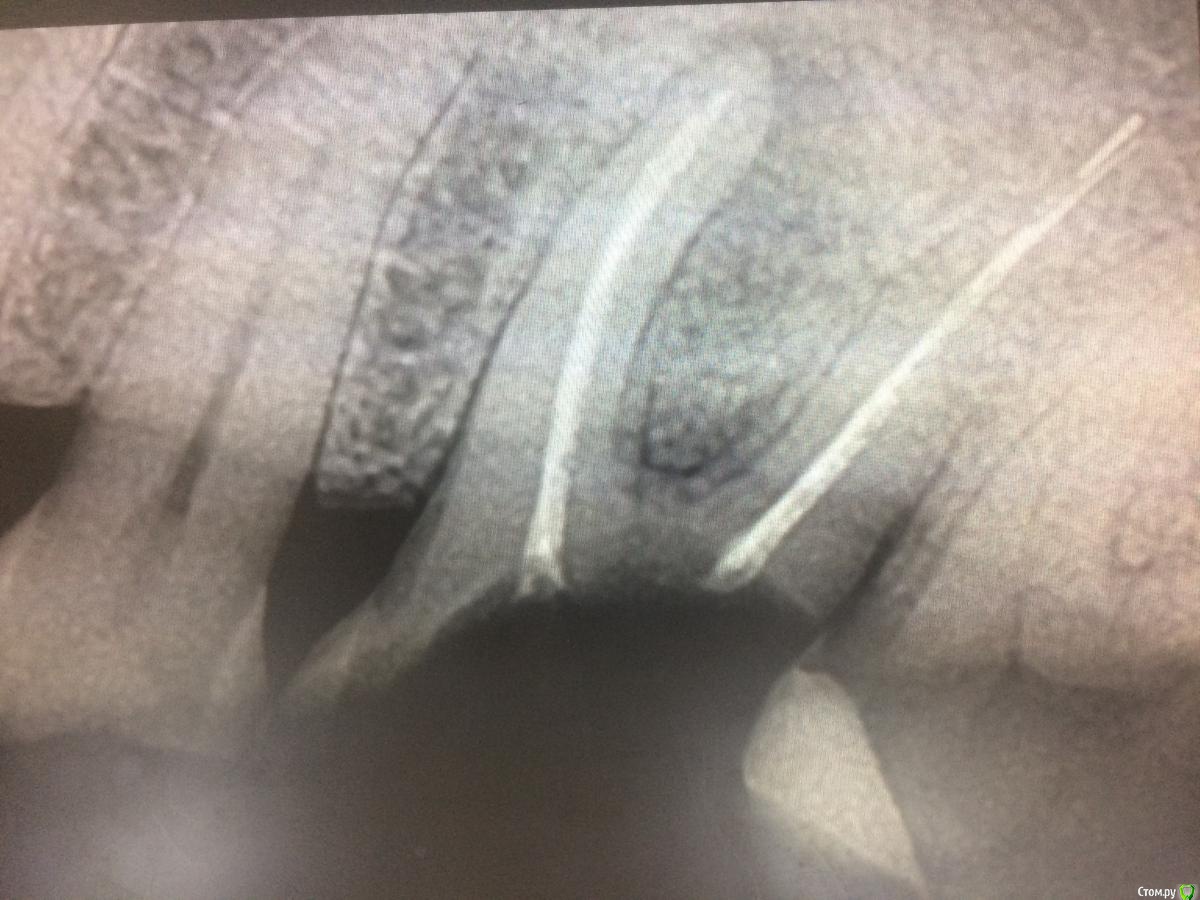

xMeDx Опубликовано 30 января, 2019 Поделиться Опубликовано 30 января, 2019 (изменено) Здравствуйте.Пришла пациентка на удаление .Сделали снимки .В дистальном корне на снимке 4.6 инструмент.Удалил и обнаружил после удаления инструмент ещё и за апексом язычного .Работаю пол года.Подскажите как удалить инструменты и стоит ли их удалять если пациентка с таким зубом проходила 15 лет ? Изменено 30 января, 2019 пользователем xMeDx Ссылка на комментарий